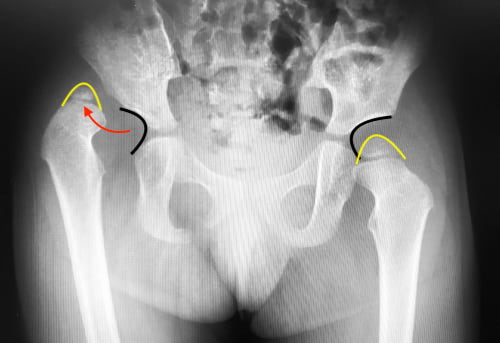

診断

日本では、乳児健診で小児科医が開排制限などの所見から脱臼を疑い、整形外科に紹介されて、そこで画像検査を行って診断されるのが一般的です。出生した児全員に対して、1ヶ月健診の時に超音波検査を行っている病院もあります。いずれにしても確定診断には画像検査が必要です。

画像検査

この病気は早く発見するほど治しやすいので、まだ軟骨でできている股関節でも診断できる超音波検査が主役です。しかし日本では訓練を受けた医師が少ないため、限られた医療機関でしか行われていません。当科では4ヶ月健診に来られた児全員に超音波検査を行っています。

レントゲン